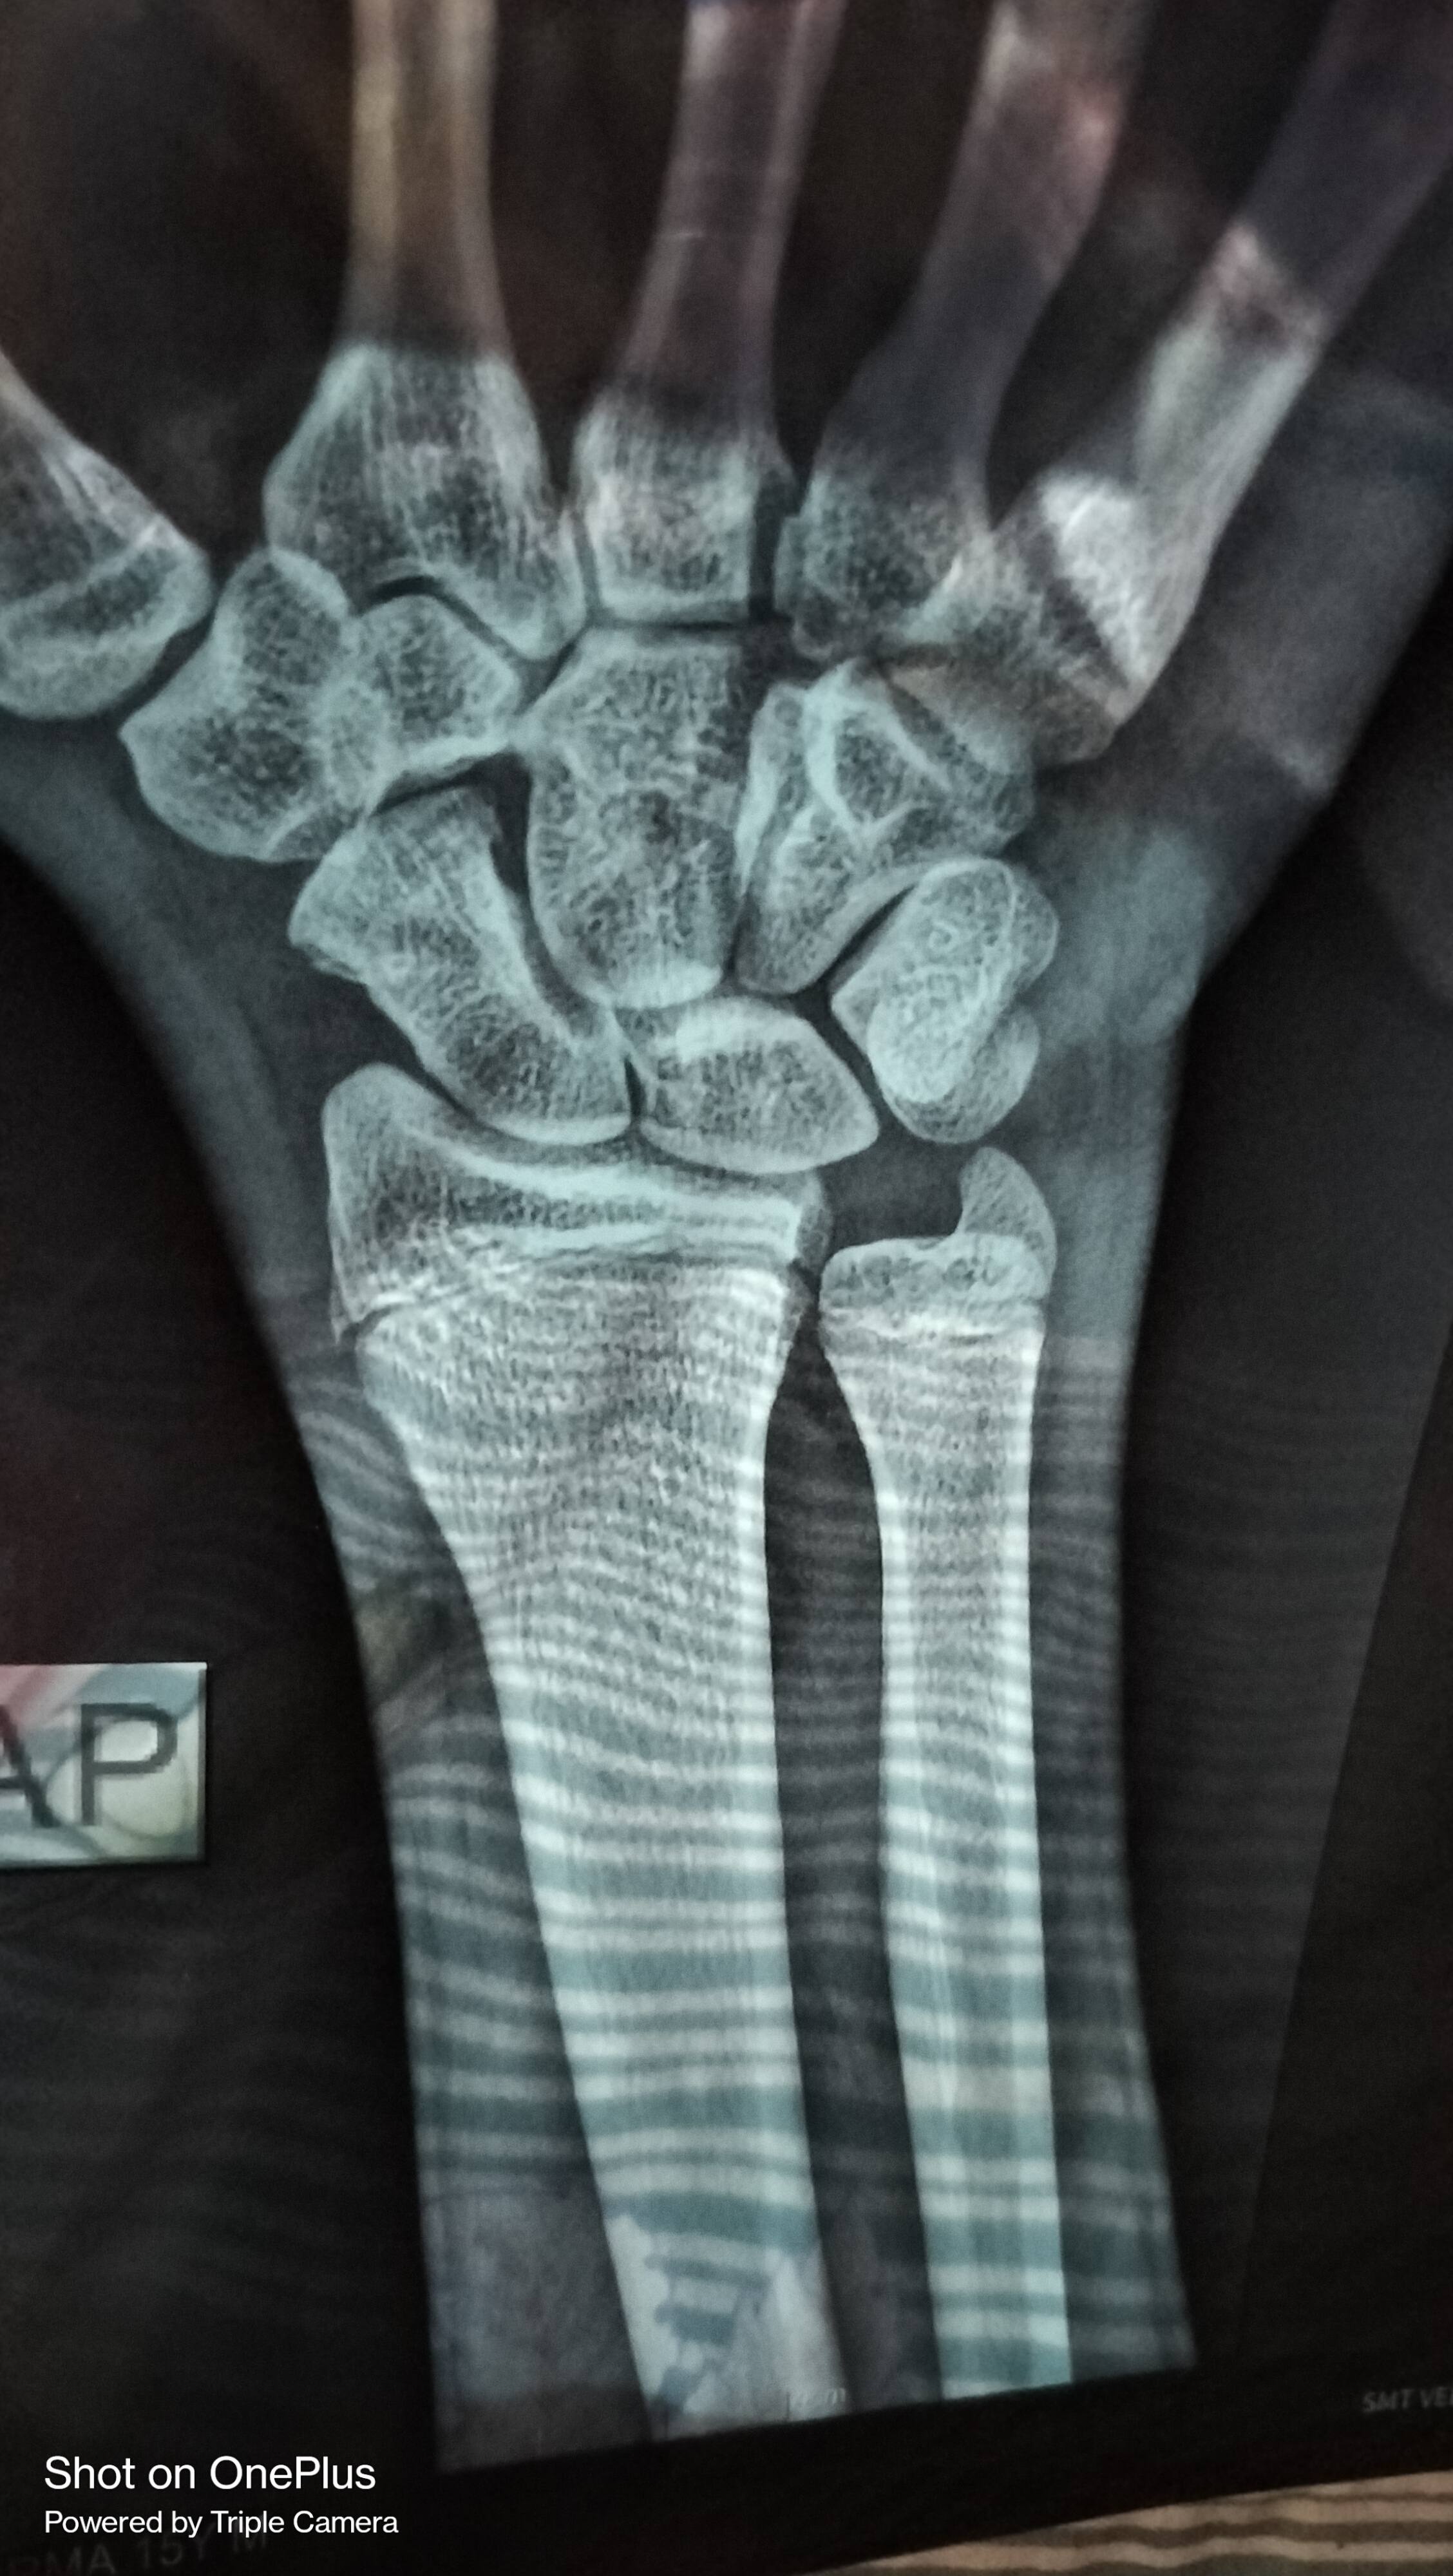

Sir 3 month pahle scaphoid fracture hua tha

Tab dhyan nahi Diya tha ab plaster kraya h

Kya plaster se sahi ho jayega ya operation karana hoga